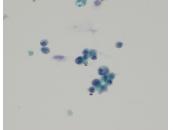

第35回日本臨床細胞学会九州連合会学会(宮崎)スライドカンファレンス症例2

種別:消化器・口腔

出題:佐賀大学医学部 病因病態科学講座 臨床病態病理学分野 力武 美保子 先生

| 年齢 | 60歳代 | 性別 | 女性 |

| 採取部位 | 肝内胆管(B5) | 採取方法 | ENBDチューブより採取した胆汁 |

既 往 歴:6年前に進行大腸癌に対し、右半結腸切除術後。

現 病 歴:大腸癌の術後フォロー中に肝内胆管(B5,B4)の拡張を認めた。精査目的にERCPが行われ、B5にENBDチューブが留置された。

| 正解 | 3.腺癌(大腸癌の転移) |

| 1.肝内結石症 | 1件 | (1.0%) | |

| 2.腺癌(胆管細胞癌) | 36件 | (37.1%) | |

| 3.腺癌(大腸癌の転移) | 37件 | (38.1%) | |

| 4.IPNB | 5件 | (5.2%) | |

| 5.腺扁平上皮癌 | 18件 | (18.6%) | |

| 投票総数 | 97件 | (100%) |